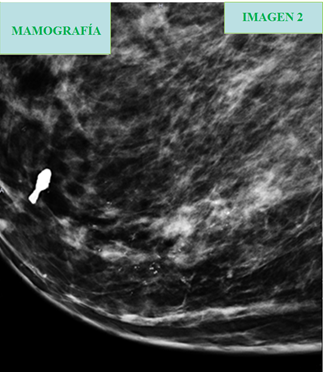

La mamografía es la primera técnica de elección para detectar el cáncer de mama en mujeres mayores de 30 años, con una sensibilidad del 90-95%. Posteriormente, se podrán hacer otras pruebas radiológicas para confirmar o descartar los hallazgos encontrados en la mamografía.